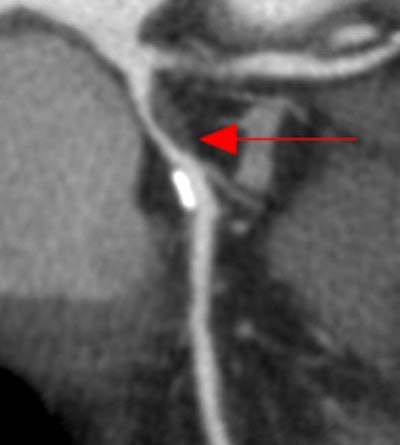

| Coronary CT angiography displayed as curved multiplanar reformation shows significant stenosis in the proximal left anterior descending coronary artery caused by noncalcified plaque. The lesion was correctly identified by the algorithm, and a true-positive detection mark (red arrow) was deployed. |